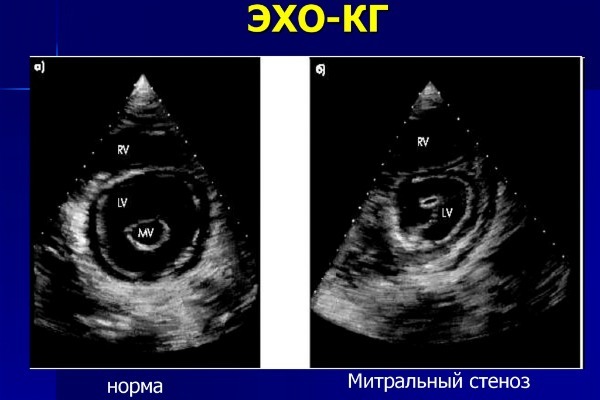

- Врожденные пороки развития: дефекты перегородок, незаращение овального окна или Баталова протока, тетрада или пентада Фалло. Все эти пороки характеризуются наличием аномального кровообращения из-за дефекта в стенке сосуда. На УЗИ выявляется эхонегативное (темное) образование, посредством которого осуществляется аномальное сообщение отделов сердца.

- Приобретенные пороки: дефекты клапанов, наличие вегетаций. При этом клапанные листки смыкаются не полностью либо срастаются между собой, образуя воронку. Также возможно наличие вегетаций – нарастания на створках (результат воспалительного процесса).